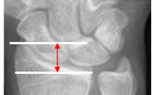

Altura’longitud radial promedio

11mm